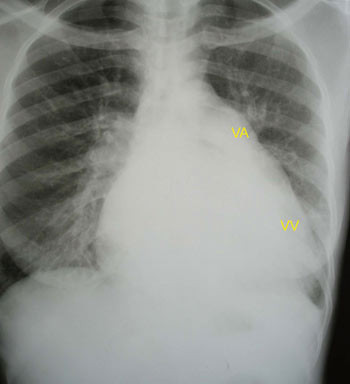

Hivpositiv 41 år gammel mann ble innlagt etter to uker med økende tungpust og ubehag i brystet. Ved undersøkelse var han medtatt, blodtrykk ble målt til 95/65 mm Hg, puls 125/min, respirasjonsrate 44/min. Han hadde ortopné og halsvenestuving. Lungene var klare ved auskultasjon, og det ble påvist hepatomegali uten perifere ødemer. Hjertetonene var fjerne, det var ingen bilyd, og ictus var ikke palpabel. EKG viste sinustakykardi. Røntgen thorax viste uttalt kardiomegali (fig 1a).

De mest aktuelle differensialdiagnosene ble vurdert å være dilaterende/hivassosiert kardiomyopati eller tuberkuløs perikarditt. Røntgen thorax alene er ikke nok til å skille mellom tilstandene (fig 1b). Legen ved lokalsykehuset sto overfor et dilemma: Skulle han satse på diuretika eller gi væske? Diuretika kan være svært uheldig for en pasient med perikardvæske og truende tamponade, som er avhengig av å opprettholde fyllingstrykket. De kliniske tegnene og et normalt EKG gjorde at mistanken om perikardeffusjon var stor.